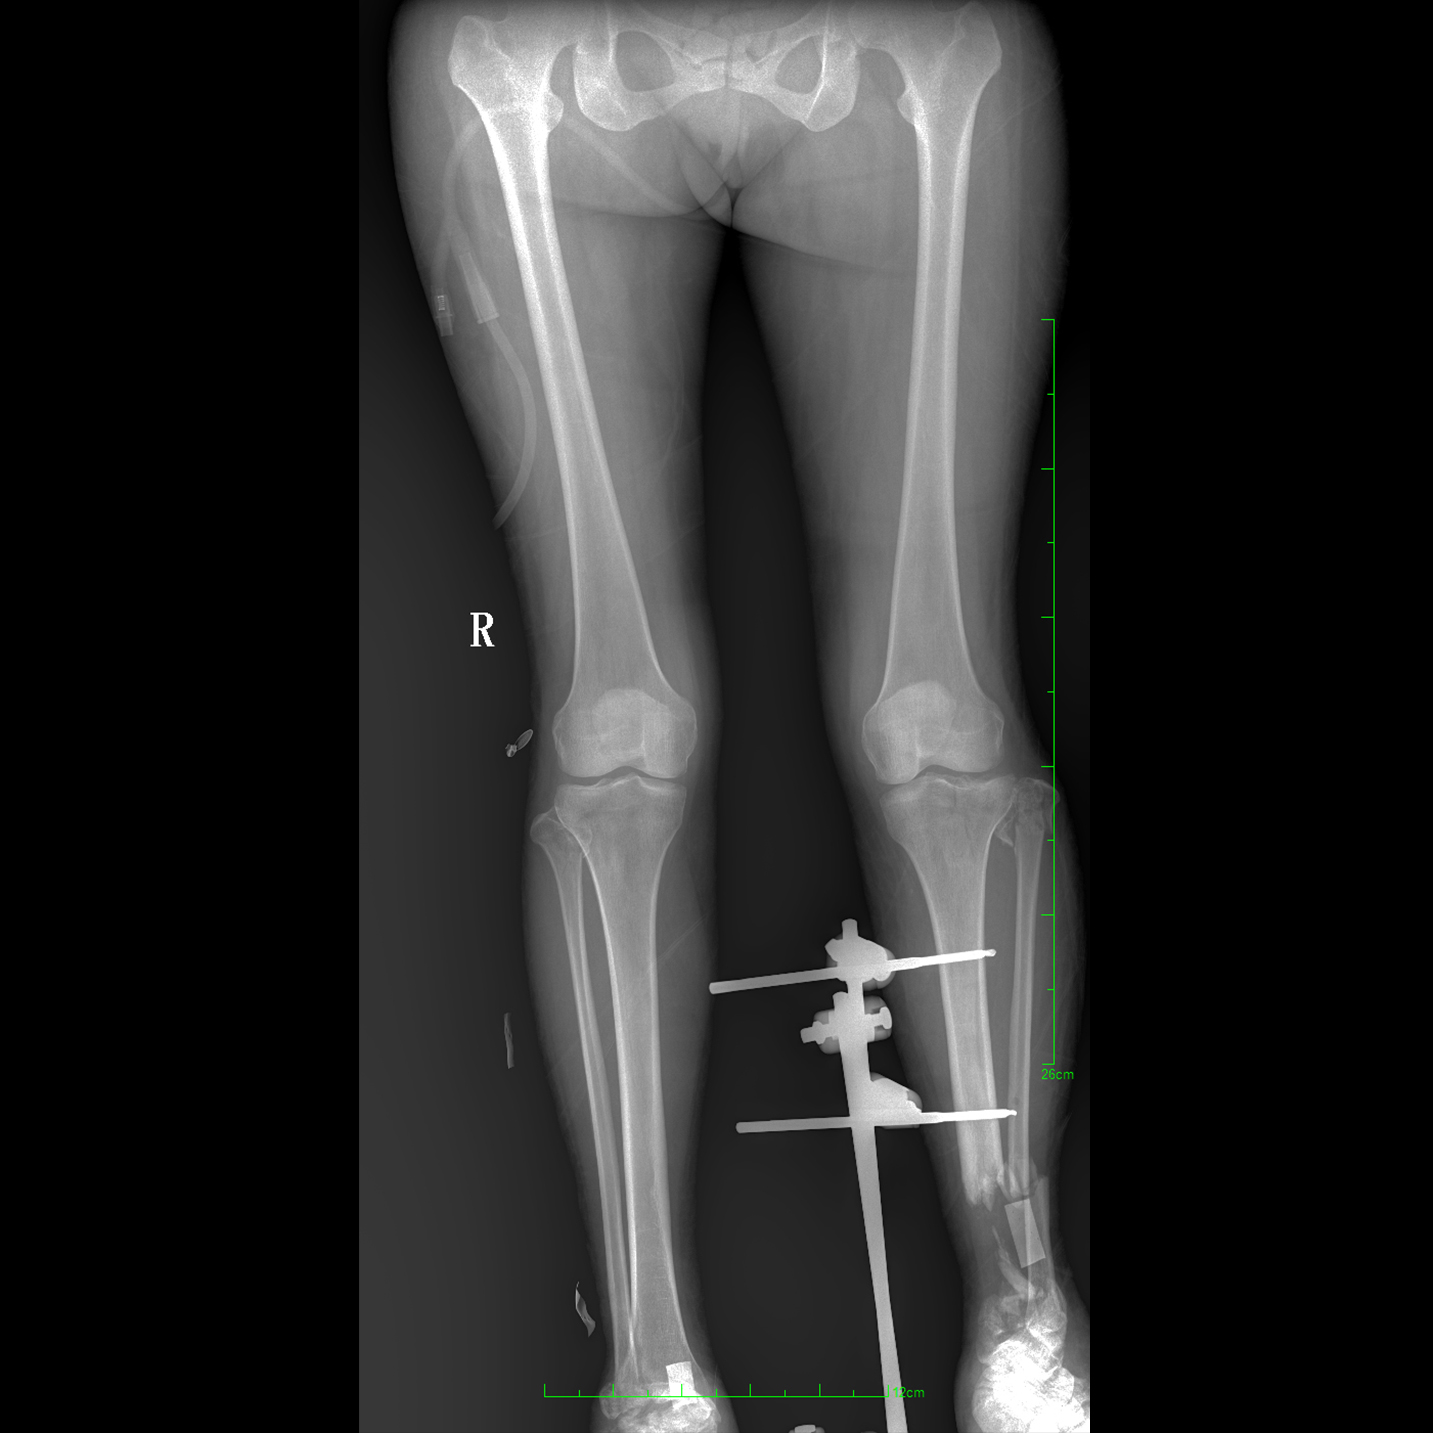

支持全脊柱攝影、雙下肢攝影、脊髓造影、復雜創(chuàng)傷、人工關節(jié)置換、關節(jié)損傷的修復重建等大視野臨床應用

17"*34"有效視野,一次成像不拼接。相較于多張攝影再軟件拼接的DR設備,PLX8600解決了拼接圖像存在密度不均勻,拼接處圖像配準和放大效應等問題,給臨床帶來了大視野影像解決方案,可一次性覆蓋全脊柱或雙下肢影像。

除常規(guī)靜態(tài)攝影外,PLX8600大平板具備動態(tài)透視和點片功能,透視采集功能可支持大視野、多角度的可視化觀察。通過可視化的動態(tài)影像,配合點片功能,能夠很好的觀察復雜部位病灶,有效的抓取關鍵幀,降低患者多次攝片的概率。如:全脊柱狀態(tài)評估、長骨關節(jié)活動度、下肢靜脈造影瓣膜功能評估、消化道功能評估、脊髓造影等更多大視野臨床應用。